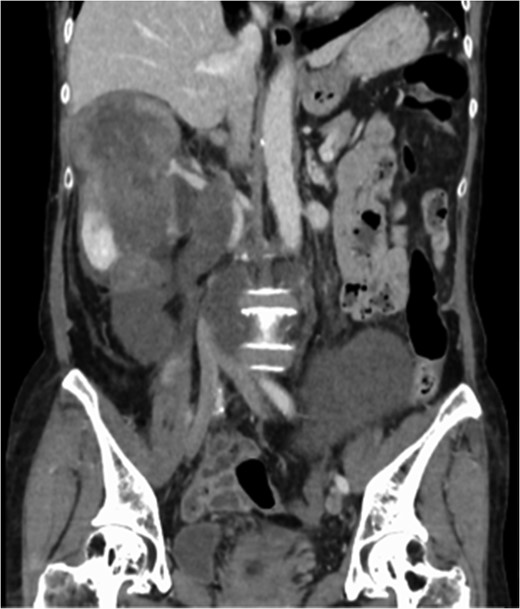

A 60-year-old female visited a clinic because of abdominal distension. She noticed abdominal distention one year prior to her clinical visit, but she left it for a year. Gradual enlargement of the mass eventually made her decide to see a doctor. Enhanced abdominal computed tomography (CT) revealed large retroperitoneal tumors. Mini-laparotomy and tumor biopsy confirmed her diagnosis as dedifferentiated liposarcoma, then she was referred to us for further examination and treatment. A multidetector CT scan revealed a hypodense mass in the retroperitoneum, with a size of ~30 × 20 cm2. The tumor appeared to invade the duodenum, head of the pancreas, right kidney, IVC and abdominal aorta (Fig. 1). The IVC was almost occluded by the tumor, but venous return from the lower extremities beyond the tumor was observed through collateral veins around the tumor (Fig. 2). The tumor invaded the abdominal aorta just below the left renal artery to the common iliac artery bifurcation, although the root and entire length of SMA appeared to be free from the tumor (Fig. 3). She underwent en bloc resection of the RL with resection of the right kidney, duodenum, head of the pancreas, a portion of the inferior IVC and abdominal aorta. Ax-F & F-F bypass was performed for vascular reconstruction using poly-tertrafluoroethylene (PTFE) to maintain the blood flow to the both lower extremities (Fig. 4). The lower abdominal aorta and both sides of common iliac arteries were resected with the tumor. The proximal stump of the abdominal aorta was closed with a running suture and covered by the omentum. The IVC was resected from just below the left renal vein to the common iliac veins. Reconstruction of the venous system including IVC and common iliac veins was not performed because venous collateral pathways had already developed sufficiently. Child’s reconstruction was performed after pylorus-preserving pancreatoduodenectomy. The duration of the surgery was 19 h 22 min, and blood loss was 4 811 mL, requiring 1680 mL of red blood cell transfusion. The tumor was 33 × 20 × 13 cm3 in size, weighed 4800 g, and had a fibrous capsule (Figs 5 and 6). Pathological examination revealed a dedifferentiated liposarcoma with negative margin (Fig. 7). Tumor invaded the pancreatic capsule, the renal capsule, the adventitia of the IVC and the abdominal aorta and infiltrated into the muscularis propria and focally into lamina propria of the duodenum. Edema of the both lower extremities was noted as postoperative complication, but that was gradually resolved by diuretics. The patient was discharged 37 days after surgery without serious postoperative complications such as pancreatic fistula, as well as graft infection or obstruction of two bypasses. Currently, she remains alive and well with no evidence of recurrence at 16 months post-operation.

Multidetector CT scan (coronal view). The tumor invaded the IVC from the orifice of the right renal vein and the peripheral IVC was almost fully occluded.